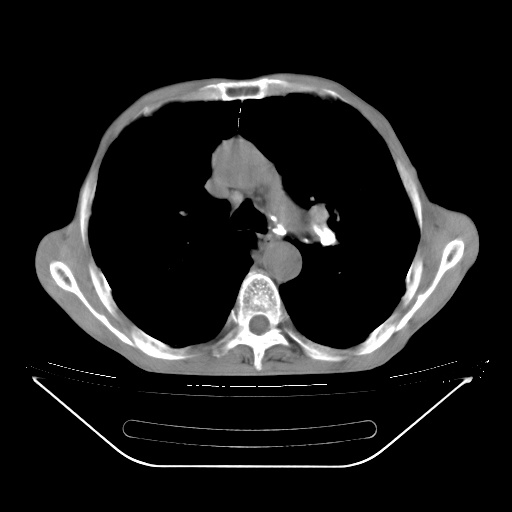

以下是引用lijuanln在2008-8-25 21:52:00的发言:[br]考虑右肺肿瘤并肺内转移,左肺上叶结核钙化;腰椎转移。

以下是引用zsl6918在2008-8-25 21:55:00的发言:[br]符合右肺周围性肺癌并肺内转移,左肺结核球。双肺肺气肿。腰椎附件转移。

以下是引用随光逐影在2008-8-25 22:03:00的发言:[br]1)考虑右肺下叶周围性肺癌并肺内转移,腰椎附件转移。2)左上肺结核(结核球形成)。3)双肺肺气肿(多发肺大泡形成)。4)双肺门区及纵隔内多发淋巴结钙化。

以下是引用qc80012345在2008-8-26 6:14:00的发言:[br]符合右肺周围性肺癌并肺内转移,左肺结核球。双肺肺气肿。腰椎附件转移。